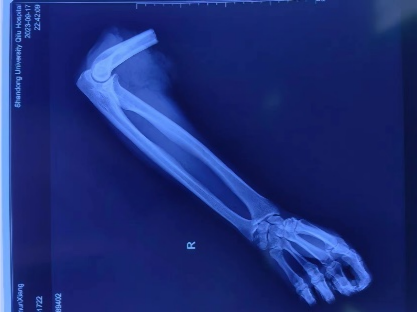

齐鲁医院手足外科等多学科联合成功救治1例上臂离断伤患者

鲁网9月26日讯 9月18日夜间,1例因机器挤压伤致右上臂离断的患者由菏泽紧急送到山东大学齐鲁医院急诊科。由于患者创伤大、失血多,病情危重,在急诊科、手足外科、手术室、麻醉科多团队、高效率联合协作下,开通绿色通道,由急诊室直接送入手术室实施手术,最终患者手臂再植成功。

大肢体离断,6—8小时内重建肢体血液循环是肢体成活的关键。为了争取手术黄金时间,手足外科主任朱磊迅速统筹安排,麻醉科主任齐峰、手术室科护士长翟永华积极联动,由手足外科副主任许庆家、崔宜栋主治医师、裴艳涛主治医师、刘奔主治医师、陈斌主治医师以及进修医师张建明等,联合麻醉科张新新主治医师、手术室护士汪静怡、孙晨霞,共同组成手术团队。为了加快手术进程,争取尽早重建肢体血液循环,手术医生分为两组,同时进行清创和血管、神经、肌腱等的标记,大大节约了手术时间,在伤后6小时实现肢体通血,减少缺血再灌注损伤的发生。手术从18日23时30分开始,到凌晨5时结束,历时5.5小时,成功完成上臂离断再植手术。